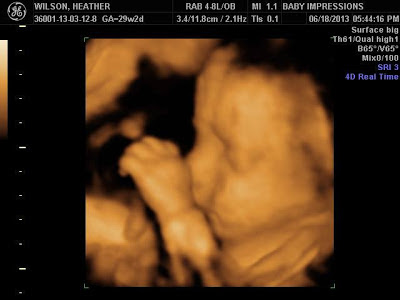

Our first appointment was with the Pediatric Cardiologist

for the ultrasound. They worked quickly because Mac was cooperating and we were

able to complete the full ultrasound in 30 minutes. We then waited while the

doctors talked. We spoke with the cardiologist who confirmed that Mac does have

Double Outlet Right Ventricle with Transposition of the Great Arteries

(DORV-TGA). He said however that the size of the left side of Mac’s heart did

not seem to be an issue. His concern is that the Mitral Valve may not be large

enough to handle the amount of necessary blood flow. He told us that at this

time he thinks that the onetime DORV-TGA procedure is still a possibility. He